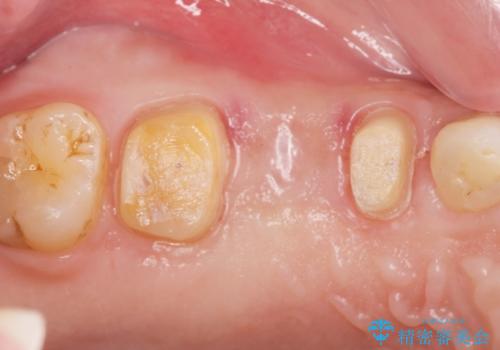

- 昨晩より歯が痛む、痛みをとって欲しいと希望され来院されました。

検査をしたところ、右上小臼歯に破折が見られ保存が難しい状況です。

抜歯を行い、咬合機能の回復を行いますが、咬合関係や非常に強い噛み合わせの問題をふまえ、咬合面をメタルにしたメタルボンドブリッジで治療を行うこととしました。